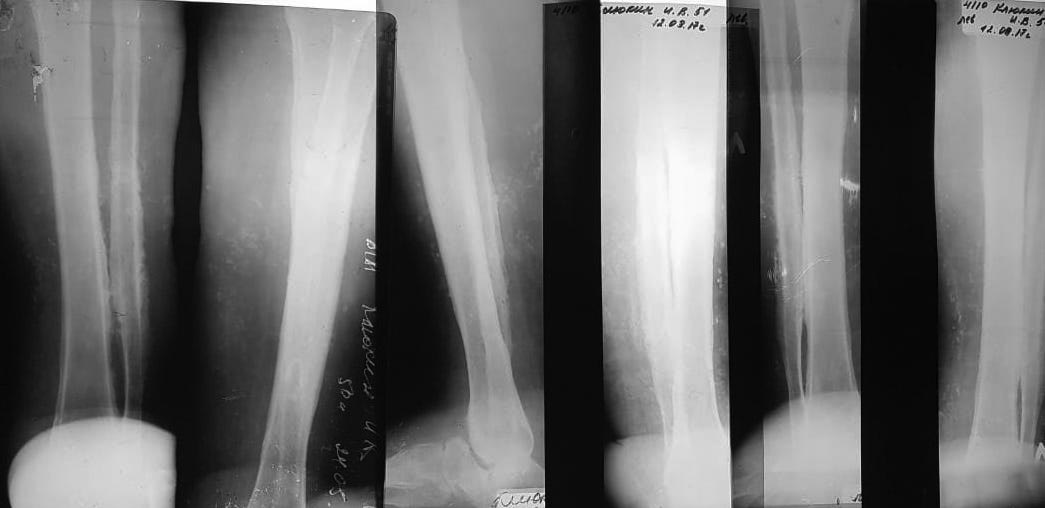

Остеомиелит

Я склоняюсь к ампутации. КТ назначена.

Анамнез - грыжа ПОП, операция, потеря чувствительности в ноге, натёр обувью, инфекция, остеомиелит. Жду КТ для определения уровня.